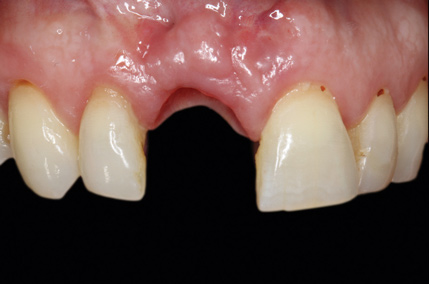

A 56-year-old female patient was referred for the evaluation of tooth No. 8 (Figure 4 and Figure 5). A periapical radiograph indicated that the tooth had undergone apicoectomy and received an excessively long post (Figure 6), and a cone-beam computed tomography (CBCT) scan of the site revealed a lack of buccal plate bone (Figure 7).

4. Facial and occlusal views of initial clinical presentation of tooth No. 8.

Figure 4

5. Facial and occlusal views of initial clinical presentation of tooth No. 8.

Figure 5